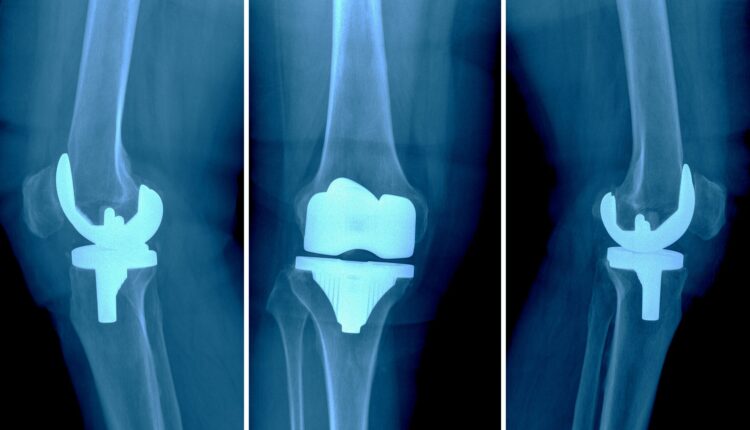

+ تعویض مفصل با پروتز

تعویض مفصل با پروتز متداول‌ترین روش در میان انواع تعویض مفصل است. در این نوع عمل آرتروپلاستی سطوح مفصلی خارج‌شده از بدن با مفصلی مصنوعی که عموما از جنس فلز، پلاستیک یا سرامیک است، جایگزین می‌شود.

آرتروپلاستی زانو

عمل آرتروپلاستی زانو را باید از جمله بهترین و موفقیت‌آمیزترین جراحی‌ها در دنیا دانست. آنچه که موجب انجام عمل آرتروپلاستی زانو می‌شود، درد زانو در قسمت پشت زانو ناشی از التهاب است. ضمن اینکه می‌تواند این درد در هر قسمتی از زانو تجربه شود. از دلایل ساییدگی و آسیب‌دیدگی مفصل باید به افزایش سن، آسیب و ضربه به زانو، آرتروز، پوکی استخوان یا روماتیسم مفصلی اشاره کرد. در مواردی که این آسیب و التهاب با فیزیوتراپی و دارو قابل درمان نباشد، عمل آرتروپلاستی زانو تنها راهی خواهد بود که می‌تواند دوباره عملکرد طبیعی زانو را به آن بازگرداند. اگر شما هم از آن دسته افرادی هستید که دردهای موجود در ناحیه زانو موجب ایجاد اختلال در فعالیت روزمره‌شان شده است، شاید بهتر باشد با مراجعه زودهنگام خود به پزشک از بروز آسیب بیشتر پیشگیری کنید. دکتر براتی با تخصص بالا در جراحی‌های مرتبط با آرتروپلاستی زانو بهترین راهنما برای شما در این مسیر خواهند بود. مطابق با دانش و تخصص بالای ایشان بهترین کسانی که می‌توانند کاندیدای خوبی برای انجام آرتروپلاستی زانو باشند، یکی از گروه‌های زیر خواهند بود: